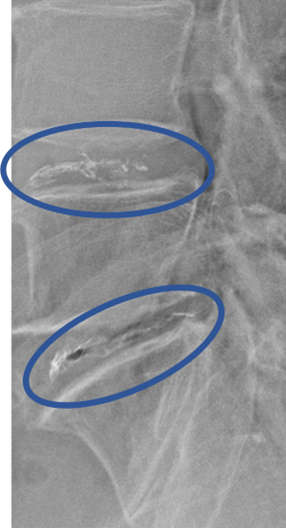

患者様と相談の元、 L4/5、5/S にセルゲル法を施行

DiscoGelを入れた後の画像になります。

治療は 20分程度で終了

回復室で休憩後、歩いて帰院されました。